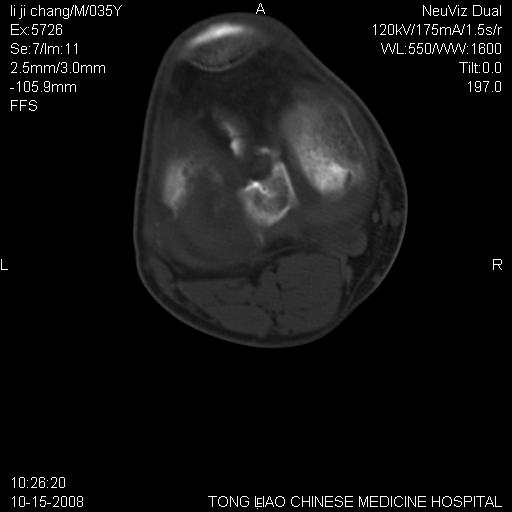

男,35岁,骨科诊断骨性关节炎。继往使用过激素,现股骨头坏死。膝关节病变,请会诊

一元论-----亦考虑为坏死

支持考虑无菌坏死

支持无菌坏死伴退行性骨关节病.

剥脱性骨软骨炎:是一种关节下软骨及软骨下骨缺血性坏死。

支持 无菌性坏死伴退行性骨关节病。